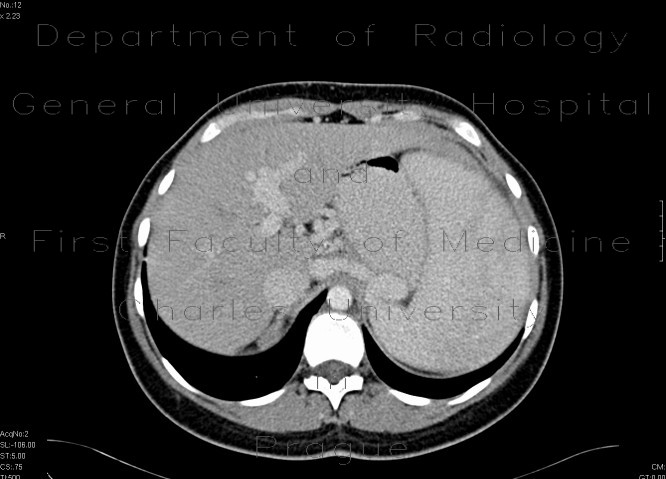

Congenital Hepatic fibrosis - Wikipedia, The Free Encyclopedia

Congenital hepatic fibrosis is an inherited fibrocystic liver disease associated with proliferation of interlobular bile ducts within the portal areas and fibrosis that do not alter hepatic lobular architecture. ... Read Article